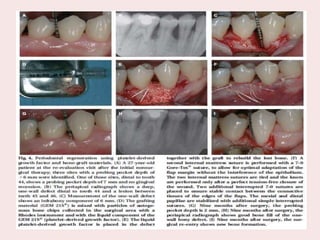

This systematic review and meta-analysis included RCTs comparing a combination of EMD with

autogenous bone graft and EMD alone for the treatment of intrabony periodontal defect with a follow-up

of 6 months. Standard difference in means between test and control groups as well as relative forest plots

were calculated for clinical attachment level gain (CALgain), probing depth reduction (PDred), and

gingival recession increase (RECinc).

Three RCTs reporting on 79 patients and 98 intrabony defects were selected for the analysis.

Statistical heterogeneity was detected as significantly high in the analysis of PDred and REC inc (I2 =

85.28%, p = 0.001; I2 = 73.95%, p = 0.022, respectively), but not in the analysis of CAL gain (I2 =

59.30%, p = 0.086).

Standard difference in means (SDM) for CALgain between test and control groups amounted to -0.34 mm

(95% CI -0.77 to 0.09; p = 0.12). SDM for PDred amounted to -0.43 mm (95% CI -0.86 to 0.01; p =

0.06). SDM for RECinc amounted to 0.12 mm (95% CI -0.30 to 0.55. p = 0.57).

Within their limits, the obtained results indicate that the combination of enamel matrix derivative and

autogenous bone graft may result in non-significant additional clinical improvements in terms of

CALgain, PDred, and RECinc compared with those obtained with EMD alone..